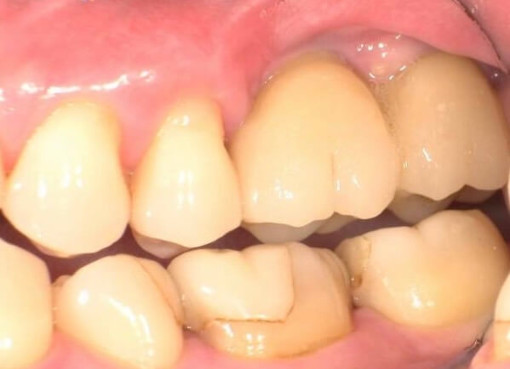

自然で美しい見た目を叶える治療

インプラント周囲の歯ぐき(歯肉)にもこだわり、自然で調和の取れた仕上がりを追求。審美的な美しさを大切にした治療を行っています。